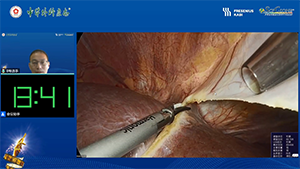

机器人辅助肝VIII段切除术

作者:陈鸣宇 | 作者单位:浙江大学医学院附属邵逸夫医院